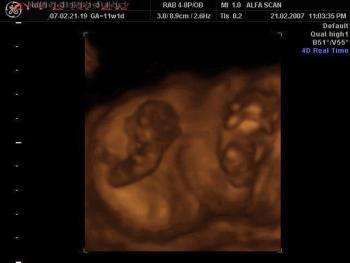

4D image of 29 weeks pregnancy, multiple anomalies: Clinch hand, omphalocoele, single atrium